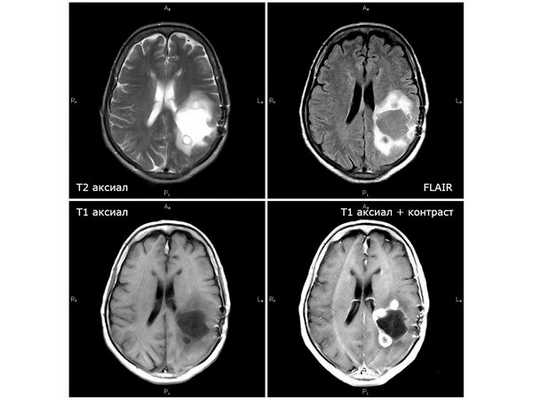

По данным МРТ головного мозга, в течение четырёх месяцев от начала лучевой терапии отмечался период улучшения. Однако несмотря на проведённый второй этап лучевой терапии болезнь стала прогрессировать: по данным контрольной МРТ от 08.02.19, появились дополнительные опухолевые узлы, рост глиобластомы продолжился. 25.02.19 пациентка в экстренном порядке поступила в нейрохирургическое отделение городской больницы № 1 г. Старый Оскол с подозрением на острое нарушение мозгового кровообращения с нарастанием правостороннего гемипареза (поражения руки и ноги справа) и нарушением речи. Находилась там на стационарном лечении до 07.03.19. Жалоб не предъявляла по причине тяжёлого состояния. Проведено лечение: внутривенное введение эуфиллина, поляризующей смеси, фуросемида и дексаметазона. Нарушение речи купировано, гемипарез значительно регрессировал. Выписана в относительно удовлетворительном состоянии. Назначен приём дексаметазона по 25 мг три раза в день. По данным МРТ от 26.02.19, отрицательная динамика стремительно нарастала: увеличивался отёк, появившиеся узлы вокруг опухолевой кисты увеличились в два раза.